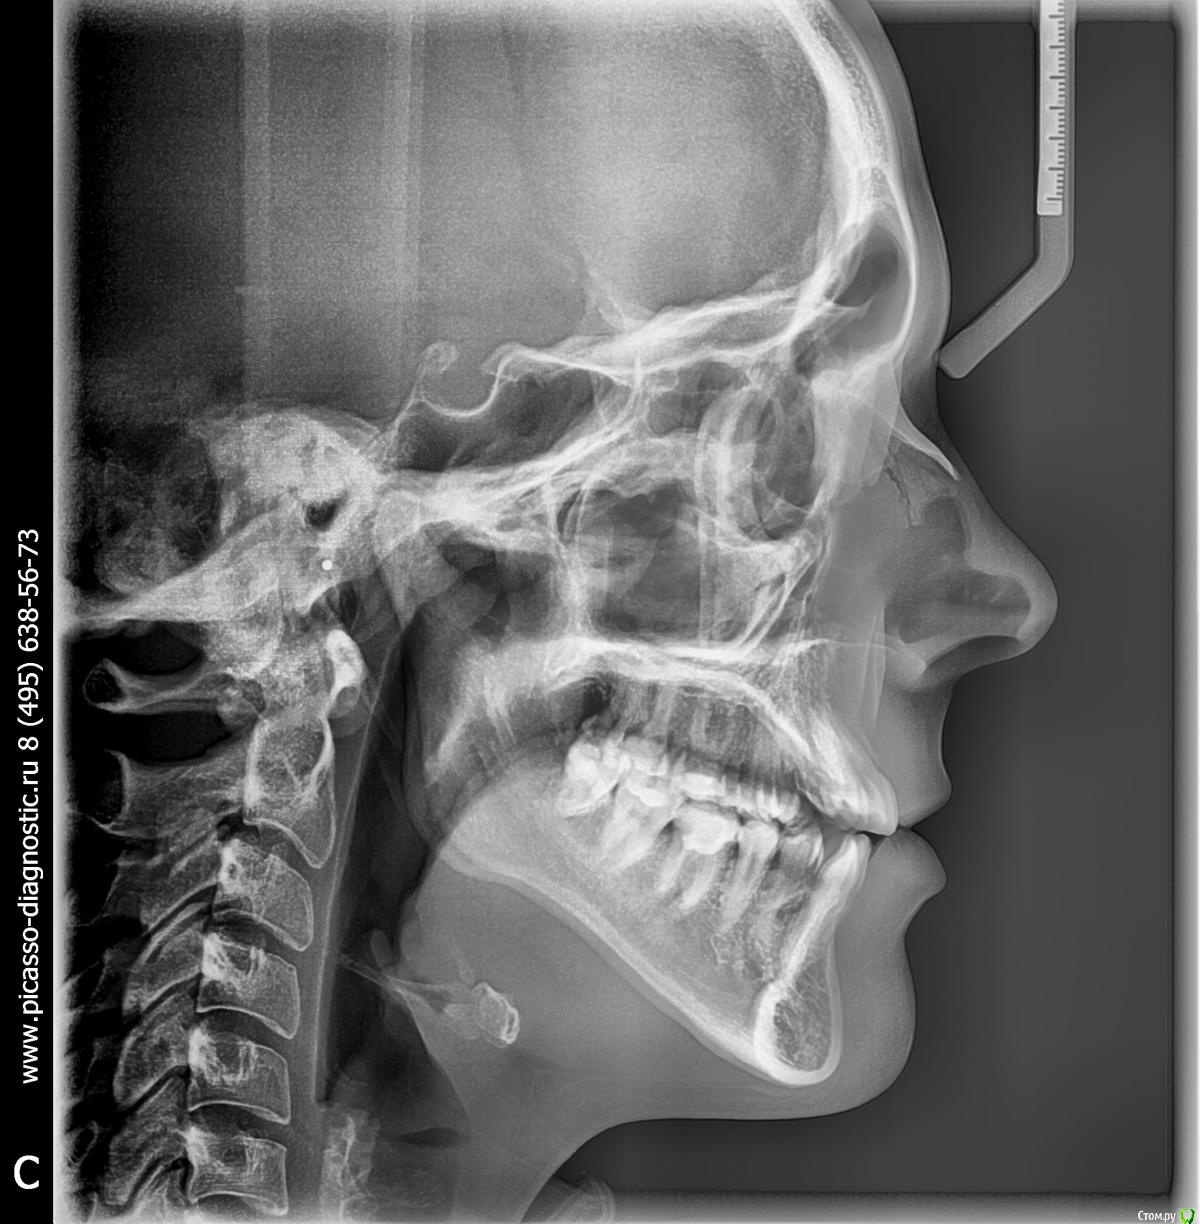

Led_9 Опубликовано 5 марта, 2015 Автор Поделиться Опубликовано 5 марта, 2015 Доброе утро! Спасибо за ответ. Снимки я не прикрепила специально, т.к. не хотела получить консультацию по плану лечения, а хотела получить совет именно на что следует обратить внимание при выборе доктора (вполне возможно что я зря засомневалась и такой подход абсолютно нормален). Но все же снимки прикрепляю. Ссылка на комментарий